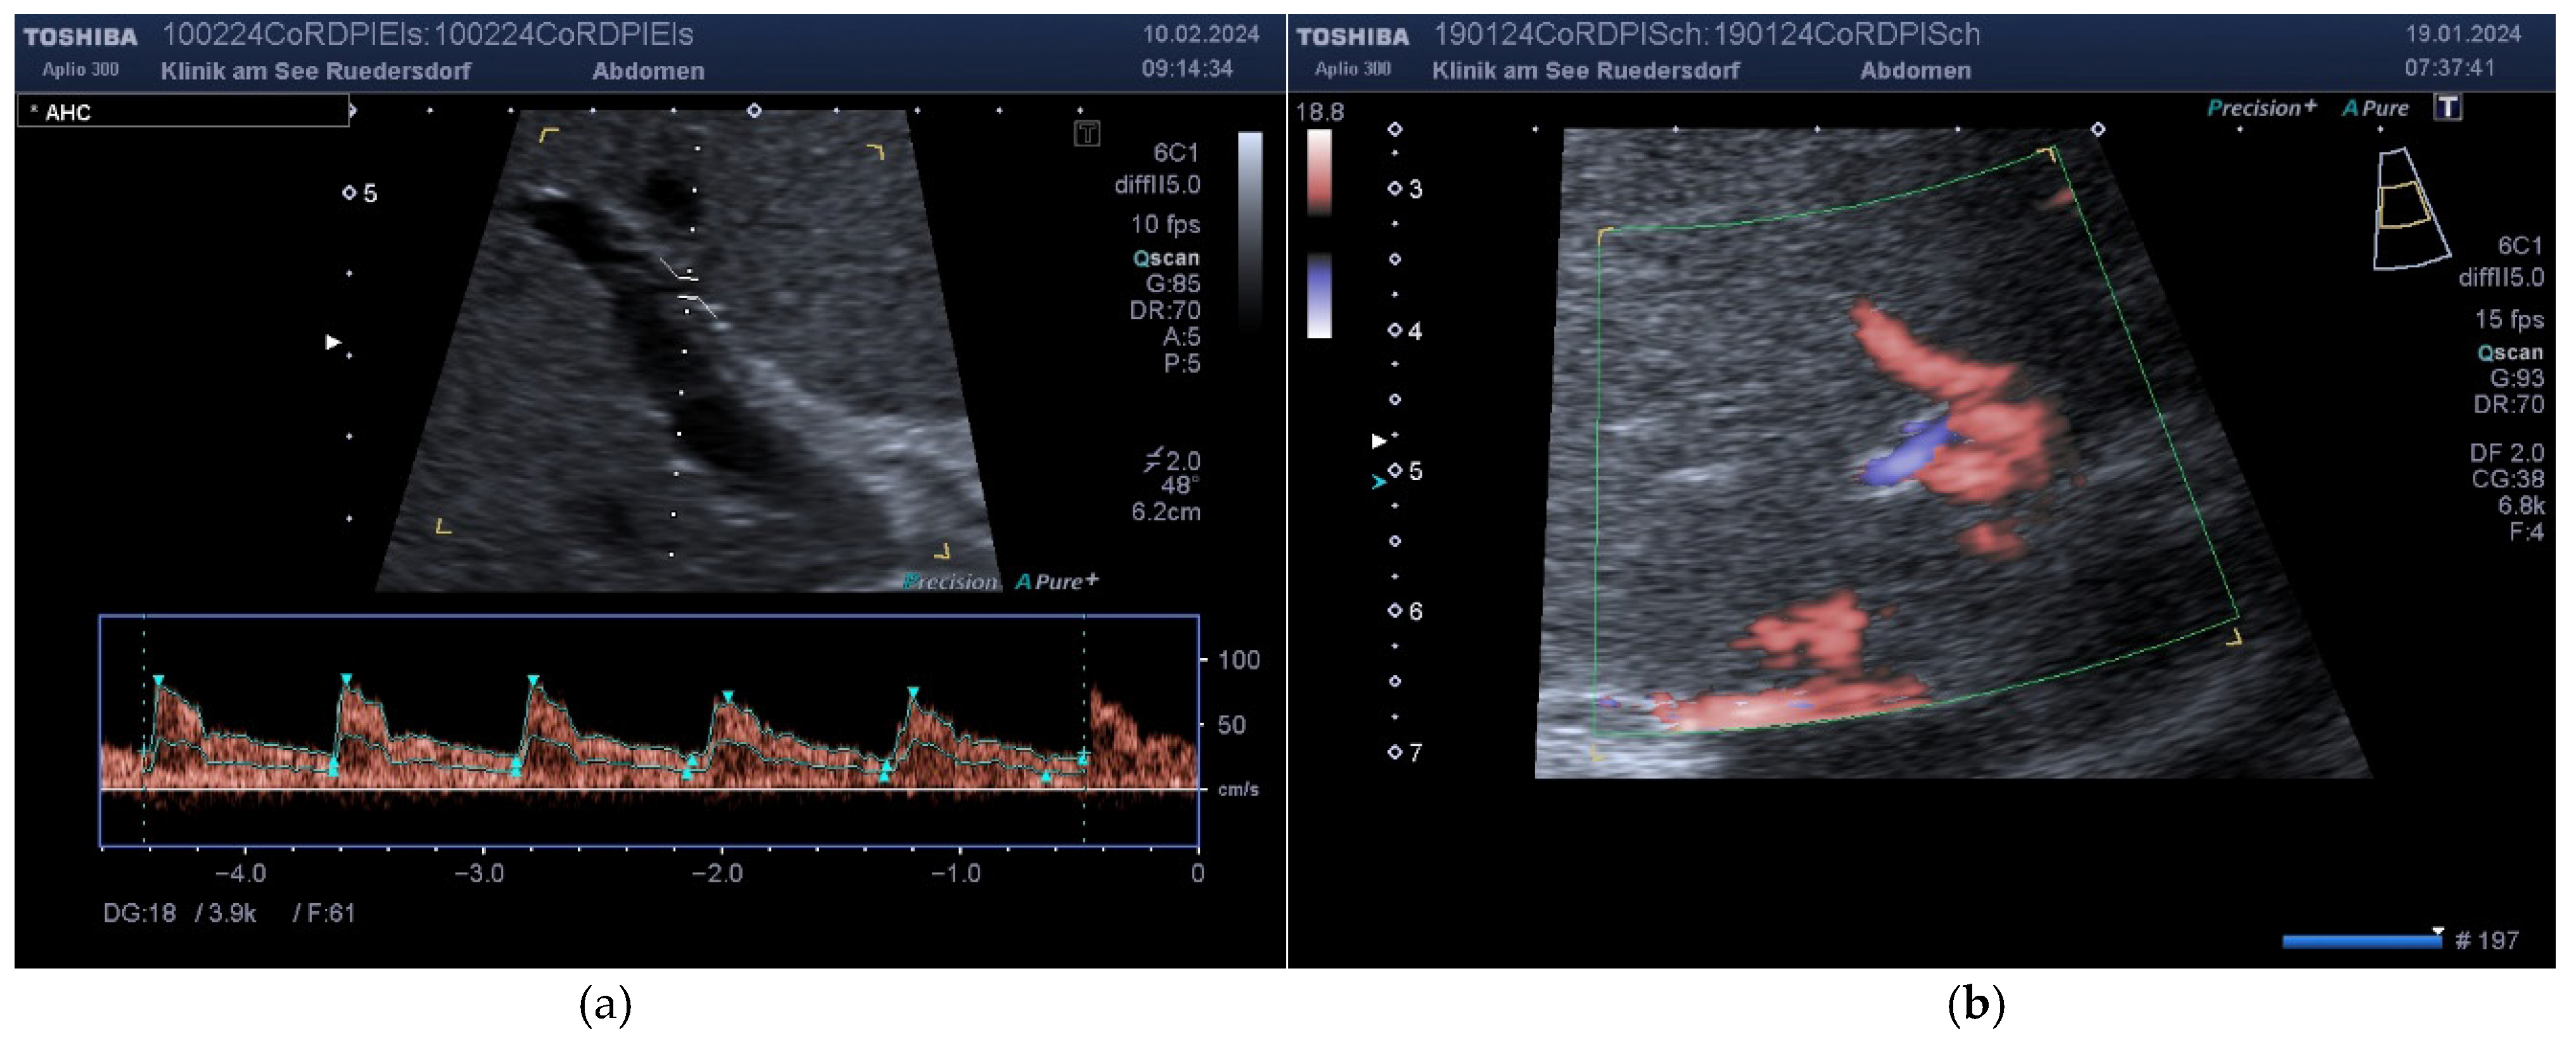

2.3.1. Determination of Vessel Diameter

2.3.2. Location of the Probe, Insonation Angle, and Doppler Window